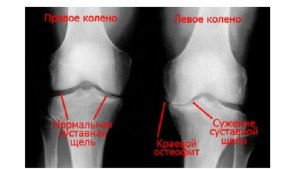

При артрозе суставов нужно больше двигаться или лежать? почему?

1. При артрозе суставов важно двигаться, так как физическая активность помогает укрепить мышцы и улучшить подвижность суставов.

2. Регулярные упражнения способствуют увеличению синовиальной жидкости в суставах, что помогает снизить трение и износ хрящей.

3. Движение также помогает уменьшить воспаление в суставах и снизить боль, связанную с артрозом.

4. Лежание наоборот может привести к ухудшению состояния суставов, так как отсутствие движения может привести к уменьшению мышечной массы и ухудшению кровообращения в суставах.

5. Однако, важно выбирать правильные виды физической активности при артрозе, чтобы избежать повреждения суставов. Например, плавание, йога и ходьба - отличные варианты умеренной физической активности для улучшения состояния суставов.

Таким образом, для лечения артроза суставов важно поддерживать активный образ жизни, делать умеренные упражнения и избегать длительного лежания без движения.